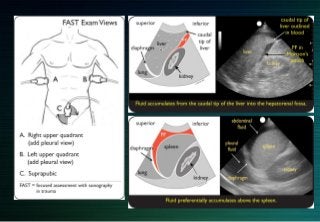

Epanchement loge rénale important

Ne pas confondre avec un épanchement dans la loge de Morison